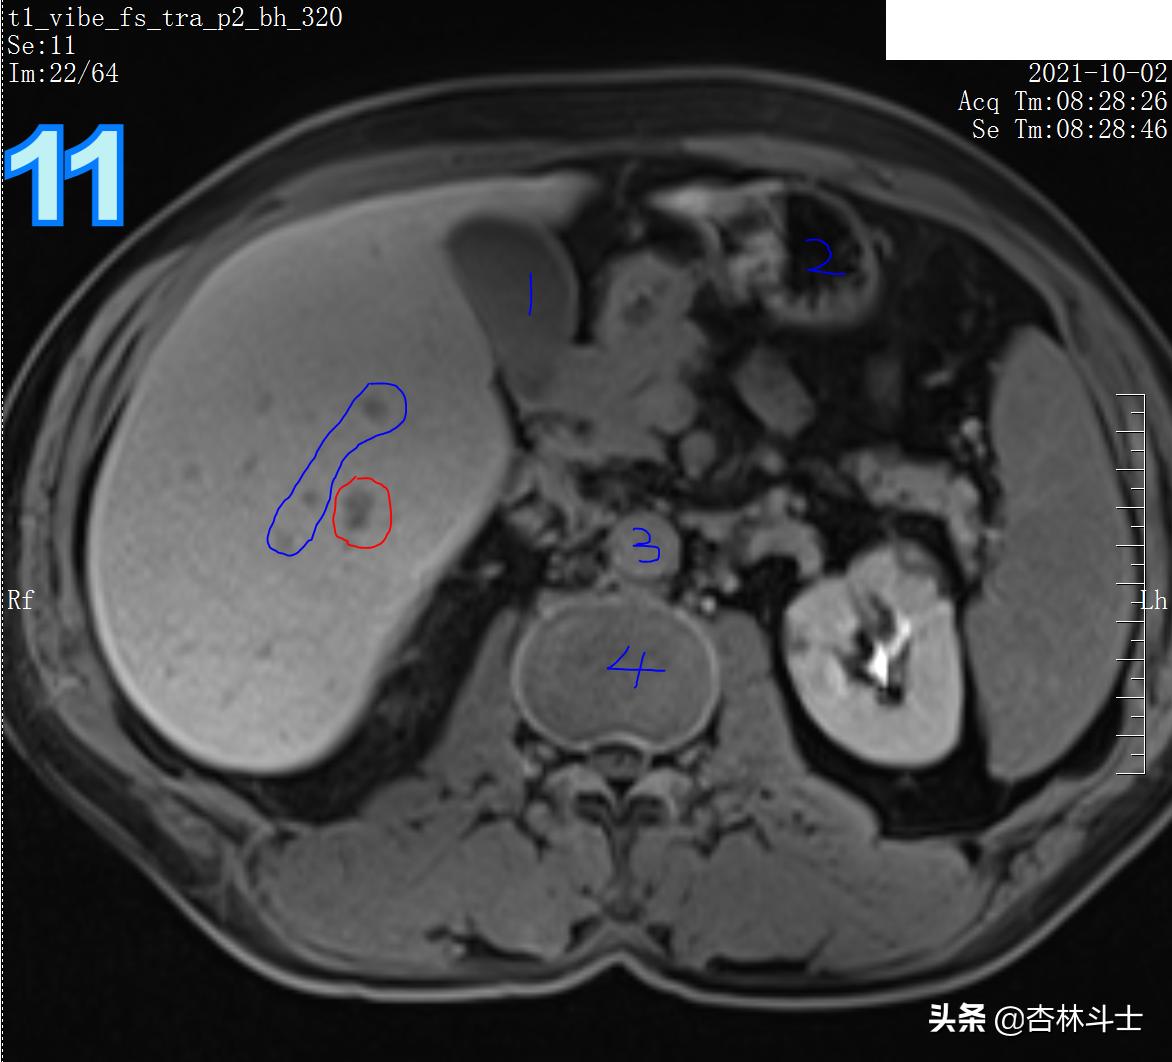

T1压脂动脉期

图8 蓝框为三根血管 ,红框为新发病灶,在T1压脂动脉期呈明显强化。

T1加权压脂

图9 蓝框为血管 红框为病灶,病灶在门静脉期呈等略低信号。蓝框血管目的为方便定位新发病灶。